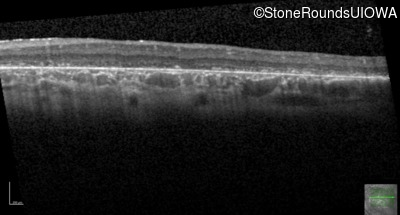

AR Stargardt Disease (IIA)

Age at visit: 6 years

This 6 year old male first experienced a loss of visual acuity at age 5. His acuity was previously normal. He is otherwise healthy.

Diagnosis & molecular findings

Disease Gene Allele 1 variant(s) Allele 2 variant(s) Inheritance mode

AR Stargardt Disease ABCA4 IVS9+1 G>A IVS37+1 G>A AR